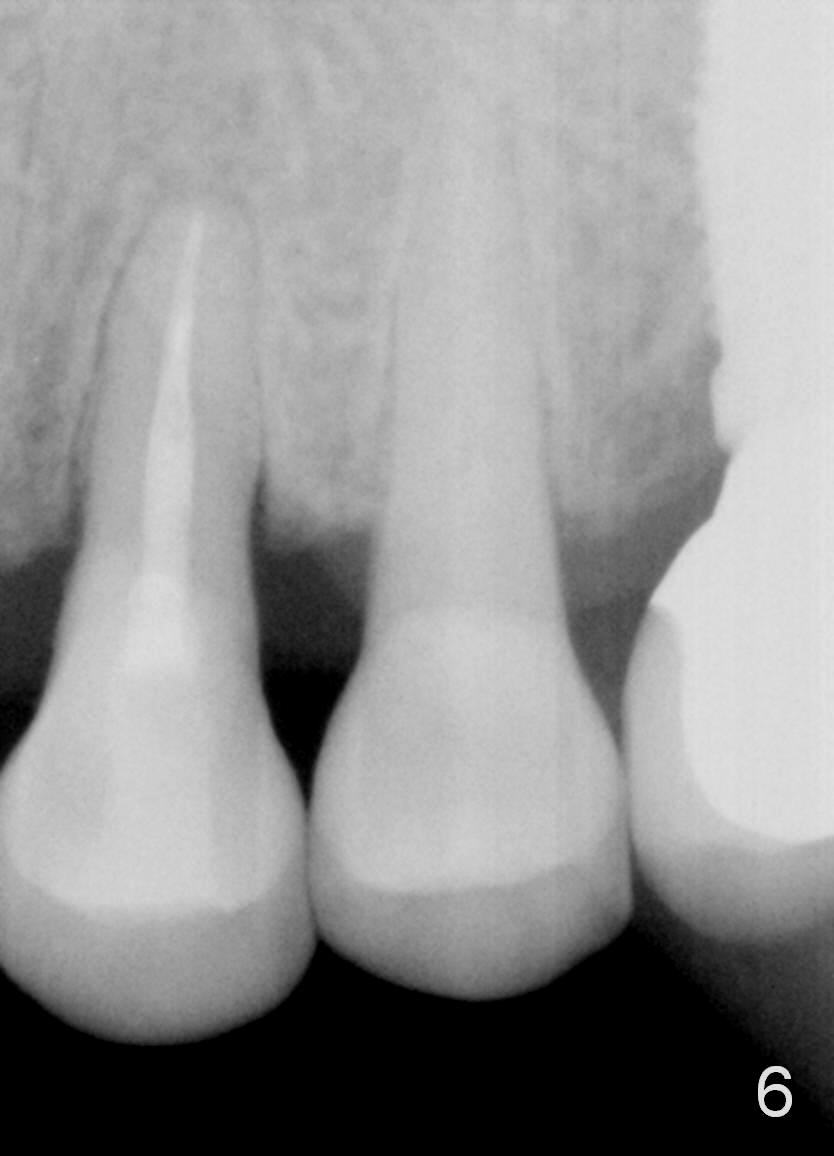

A month later, the fistula disappears (Fig.5). Effort is exerted without success to find the obliterated canal, including increasing access and removing the portion of composite which may block the opening of the canal. RCT is finished. Two months postop, the patient returns for prophy. She remains asymptomatic. There is no recurrent infection. Seven months post RCT, periapical radiolucency seems to have disappeared (Fig.6), whereas the fistula does not recur (Fig.7).